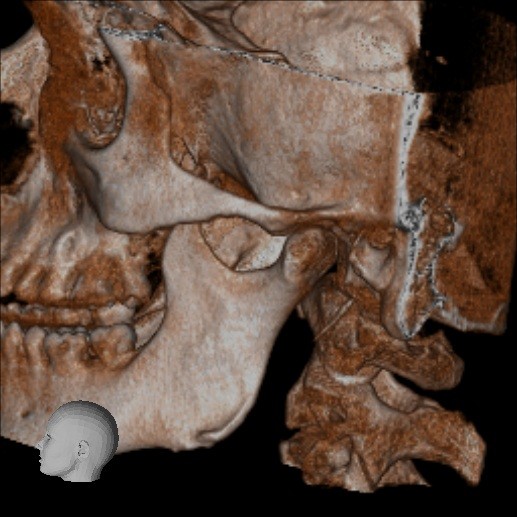

Below are some screenshots from my Cone Beam CT scan and the report linking possible ES. I have more Regular CT scans I could possibly share and/or if you would like me to get possible better angles from the Cone Beam CT scan let me know. But as of right now I’m at a loss as what to do going forward. I do have an MRI with and without contrast of the Cervical Spine Scheduled, but that’s due to the doctor’s (the doctor that dismissed it as ES and one doctor that wants to follow up and learn more on it) wanting it.

- Now onto this year, I finally got better back to full health in late November early December 2024 and sadly started to get another sinus infect in January and still no answers to why. I just happen to be watching YouTube when a Dentist had said that your teeth could be linked to sinus issues causing sinus infections and normally the only way to tell if this is the case is to get a Cone Beam CT scan. I then thought this could be another lead to find out why I keep getting sick as I did when I was 10 have my first top premolar on my left side removed against what I wanted as they said my teeth were too crowded and it needed to be removed so I could have braces (which that dentist didn’t even do my braces anyway). But I thought when he removed it if a small piece of the root was still in there as he just broke out the tooth without removing it via surgical means that that could cause an abscess in my Left Maxillary Sinus where infections always start. So, finally I was able to find a place that would give me a Cone Beam CT scan back in February of this year all while I was just starting to get sick from my infection. Anyway, I finally got the report in March and found out oddly my Left side is mostly normal other than mucus polyps, but I have a few other issues (I have attached the report below). This report is where I first found out about Eagle Syndrome as it states I might have Calcified Ligaments and further testing is needed to confirm. It was only after this report and looking up what Eagle Syndrome was that I can say I have almost every symptom that has ever been reported. Sadly, I couldn’t find anyone in my State at the time that work with Eagle Syndrome and when I did was about a week before I found this site and the doctor I did see seemed to dismiss me as another hypochondriac and you can’t have it as you don’t have Vertigo type Dizziness, my styloid are normal length and I don’t have neck pain equivalent to having to be in a neck brace. Not only this she only looked at my CT scan from a week earlier that I had got in Emergency. The Emergency visit was due to the fact at 8PM that night I had pain in my Right Mastoid Bone, and I was starting to get an earache. I went to lay down and took pain meds and an ice pack in hopes to reduce the pain and swelling. I couldn’t sleep due to the pain and came upfront about 10PM. 10:21PM I couldn’t take it anymore and started to stretch my neck and I felt a huge snap and heard a load pop, all the pain just felt like it disappeared. One minute later, I had a massive pain that spread just like when you get an IV that stings, but it felt like someone was trying to murder me and stabbed a knife into the right side of my skull. I was in so much pain that I was hunched over, and we had to have an ambulance called. I thought I was having an aneurism and my mother thought I was having a Stroke (very rare ES Symptom). When the ambulance arrived, they took my vitals, and my blood pressure was 148/110 with a pulse in the high 90’s low 100’s. Luckily the pain had subsided enough that we were able to go to emergency without the ambulance ride, but while I was in emergency the pain had spread to my left side of my head and now felt like someone had taken a clothes iron and stuck it on my head. Any breeze moving my hair was pure agony and I couldn’t lay my head on a pillow without that burning pain. According to emergency though I must have just had a Mastoid Process infection and it burst. Luckily the pain went away by the time I went to the Doctor for ES, but like I said before they were of no help.